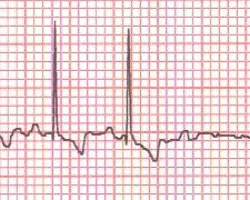

نوار قلب

به کمک دستگاه نوار قلب دامپزشکی مشکلات قلبی دام کوچک از جمله آریتمی تشخیص داده می شود. از این دستگاه در هنگام بیهوشی برای عمل های جراحی یا سایر اعمال درمانی هم استفاده می شود. کار با این دستگاه و گرفتن نوار قلب باید در محیطی انجام شود که هیچ نویزی به آن وارد نشود. نویز می تواند در درستی نتیجه این دستگاه اختلال ایجاد کند.